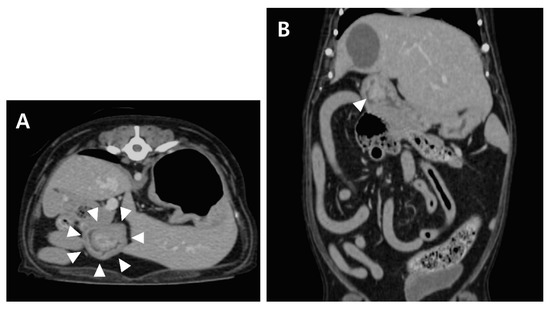

Thoracic and abdominal radiography revealed no significant findings. Abdominal ultrasonographic examination (EPIQ 5G; Philips Ultrasound, Bothell, WA, USA) revealed a solitary and round-to-oval-shaped intraluminal mass cranial to the pyloric antrum (Figure 1). In order to obtain information regarding the base of the mass, a hydrogram was obtained after feeding 500 mL of water. The mass was assumed to be sessile because its base was wide, and it showed little or no displacement during peristalsis. The patient’s gastric motility was normal, and the lesion showed mixed echogenicity.

Figure 1. Longitudinal ultrasonographic examination. A mass arising from the mucosal layer was identified (A). A sessile echogenic lesion (asterisk) with a broad base (arrow) arising from the mucosa was identified after feeding water (B). Fluid (F) is present in the stomach.